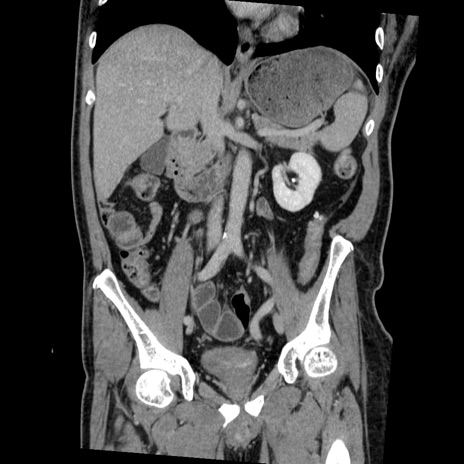

症例22(冠状断像)

【症例】50歳代男性

【主訴】腹痛

【現病歴】AVMからの被殻出血のため回復期リハ病棟入院中。 本日午後3時頃急に下腹部痛が出現した。

【既往歴】AVM、被殻出血、虫垂炎、高血圧

【身体所見】意識晴明、左半身不全麻痺、会話の理解は良好、36.5°C、腹部:膨隆、全体に板状硬、下腹部正中に圧痛点あり、反跳痛-、筋性防御不明、右下腹部にope scar

【データ】WBC 9400、CRP 0.06